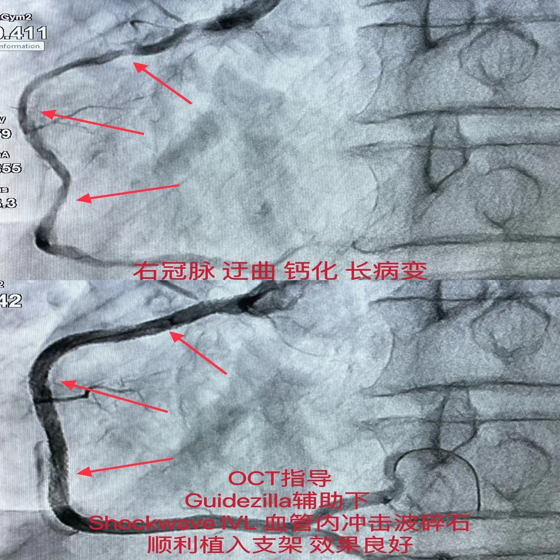

该患者于10天前,于我院开通前降支无残端CTO,右冠脉迂曲、弥漫长病变伴严重钙化,此次在OCT指导下,Guidezilla延长导管辅助下,送入Shockwave IVL冲击波球囊于病变处予8个周期80个脉冲的预处理后顺利植入支架,复查OCT结果满意,未见支架膨胀不全及贴壁不良。

根据标准操作流程,充盈4atm使球囊充分贴靠,从第一次球囊冲击波发射2个周期后,更换位置,连续8个周期以后,钙化部位球囊凹陷处消失并可正常膨胀,狭窄减轻。

术中连续治疗8个周期(80次脉冲)后,植入支架,支架贴壁良好。